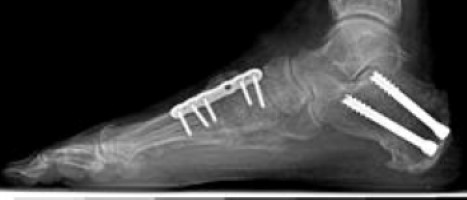

Osteotomy

X-ray of a foot as viewed from the side in a patient with a more severe deformity. This patient required fusion of the middle of the foot in addition to a tendon transfer and cut in the heel bone.